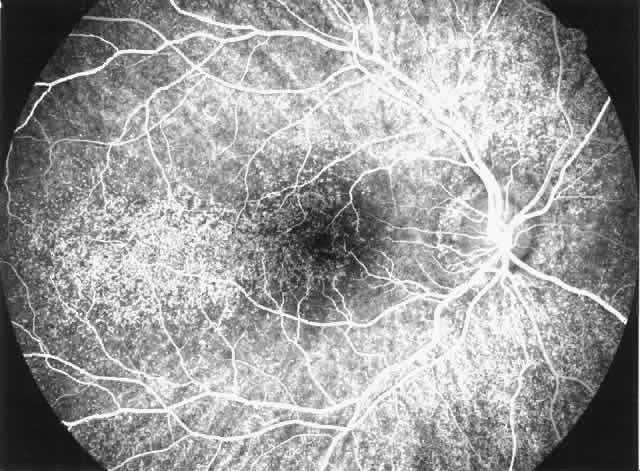

All cystinotic patients have ocular involvement, and older patients with nephropathic cystinosis are at risk of severe ocular complications. In nephropathic cystinosis, crystal deposits usually appear in the cornea within the first year of life. Initially, crystals can be identified in the anterior peripheral part of the cornea by slit lamp biomicroscopy. With time, progressive accumulation of crystals occurs throughout the corneal stroma, inducing photophobia even in young children and provoking a hazy, ground-glass appearance of the cornea in older patients.36 Crystal deposits are also formed in conjunctiva, iris, and retinal pigment epithelium.37 Focal degeneration of the retinal pigment epithelium with patchy depigmentation of the fundus may appear early in life and is generally present by age 7.37 The fundus lesions are bilateral and symmetric and involve mainly the periphery, although some patients also develop atrophic macular changes (Fig. 3). Abnormal retinal function with reduced or extinguished responses on electroretinograms and decreased visual acuity are frequent complications in older cystinotic patients.37,38 Several other complications have been described in patients with nephropathic cystinosis, including superficial punctate keratopathy, recurrent erosions, corneal vascularization, band keratopathy, tight miosis, posterior synechiae, and pupillary-block glaucoma.35,37–39

Fig. 3. Cystinotic fundus changes in a 19-year-old patient, demonstrating a pale optic disc and numerous peripheral and macular small white spots at the level of the retinal pigment epithelium. Fluorescein angiography confirmed marked degenerative changes of the retinal pigment epithelium with macular, peripapillary, and peripheral window defects.